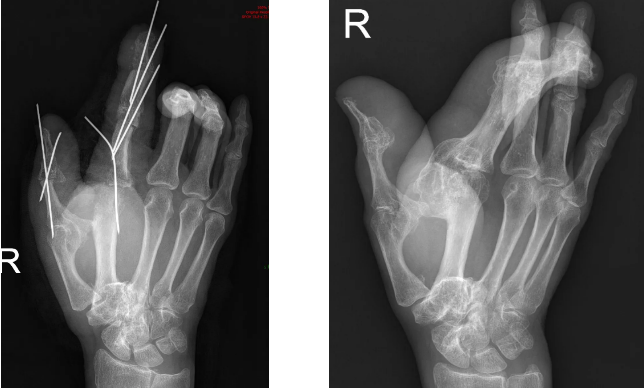

芳姨刚出生时,就被家人发现右手拇指和食指比正常要大。随着时间的推移,在手指变大的同时,偏斜也越来越严重,慢慢地,方姨的拇指和食指都不能活动了,其它三个指头的功能也受到了限制。

随着年龄的增长,指头的状况越来越差,在四处寻医之后,芳姨被确诊为“巨指症”“平时在生活中,我都不敢把手伸出来,太丑了,我怕别人会歧视我......”这个确诊,不只带来了身体上的不适,而且在芳姨的心里埋下了“自卑”的种子。50多年了,想拥有一只正常的手就像是一个遥不可及的梦想,一直深深藏在芳姨的心里。

“芳姨得的是巨指症,50多年来,畸形逐渐加重,尤其是食指极度地尺偏,给患者的手的外观、功能都带来了很大的影响。”栗主任道。

经过两个小时如绣花般的减容矫形手术,芳姨右手的食指和拇指外观接近正常,预期后期手部的功能也会得到很大改善。

栗主任告诉我们,巨指症就是手指变得巨大。分为两种类型,一是静止型,不再随儿童的发育而进展;二是进展型,与正常发育不成比例的增大。进展型在婴儿期可能没有增粗,但在幼年开始迅速发展,此型常伴有成角畸形,使手看起来跟香蕉一样,使指成“香蕉型”。